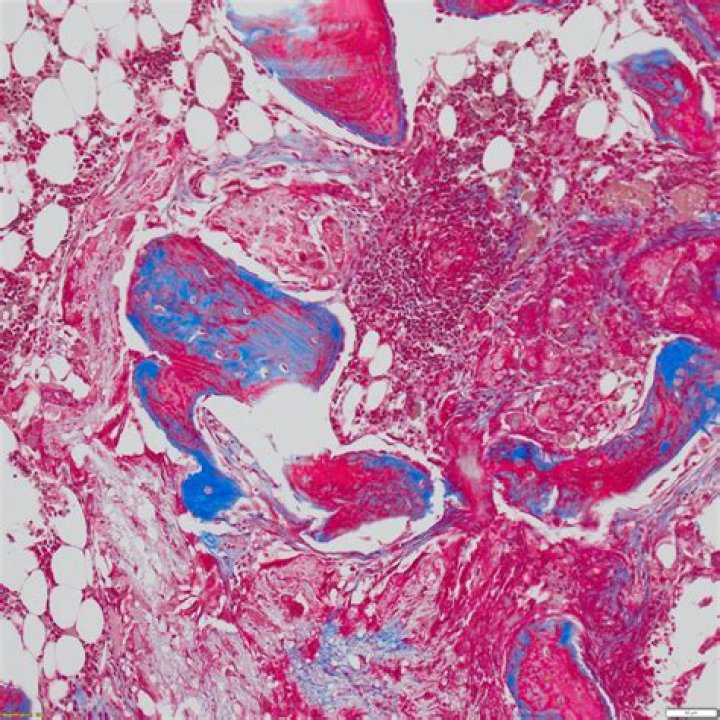

Score: 4.2/5 (64 votes) Masson's trichrome is a three-colour staining protocol used in histology. ... It is used to stain the nuclei. Solution A, al...